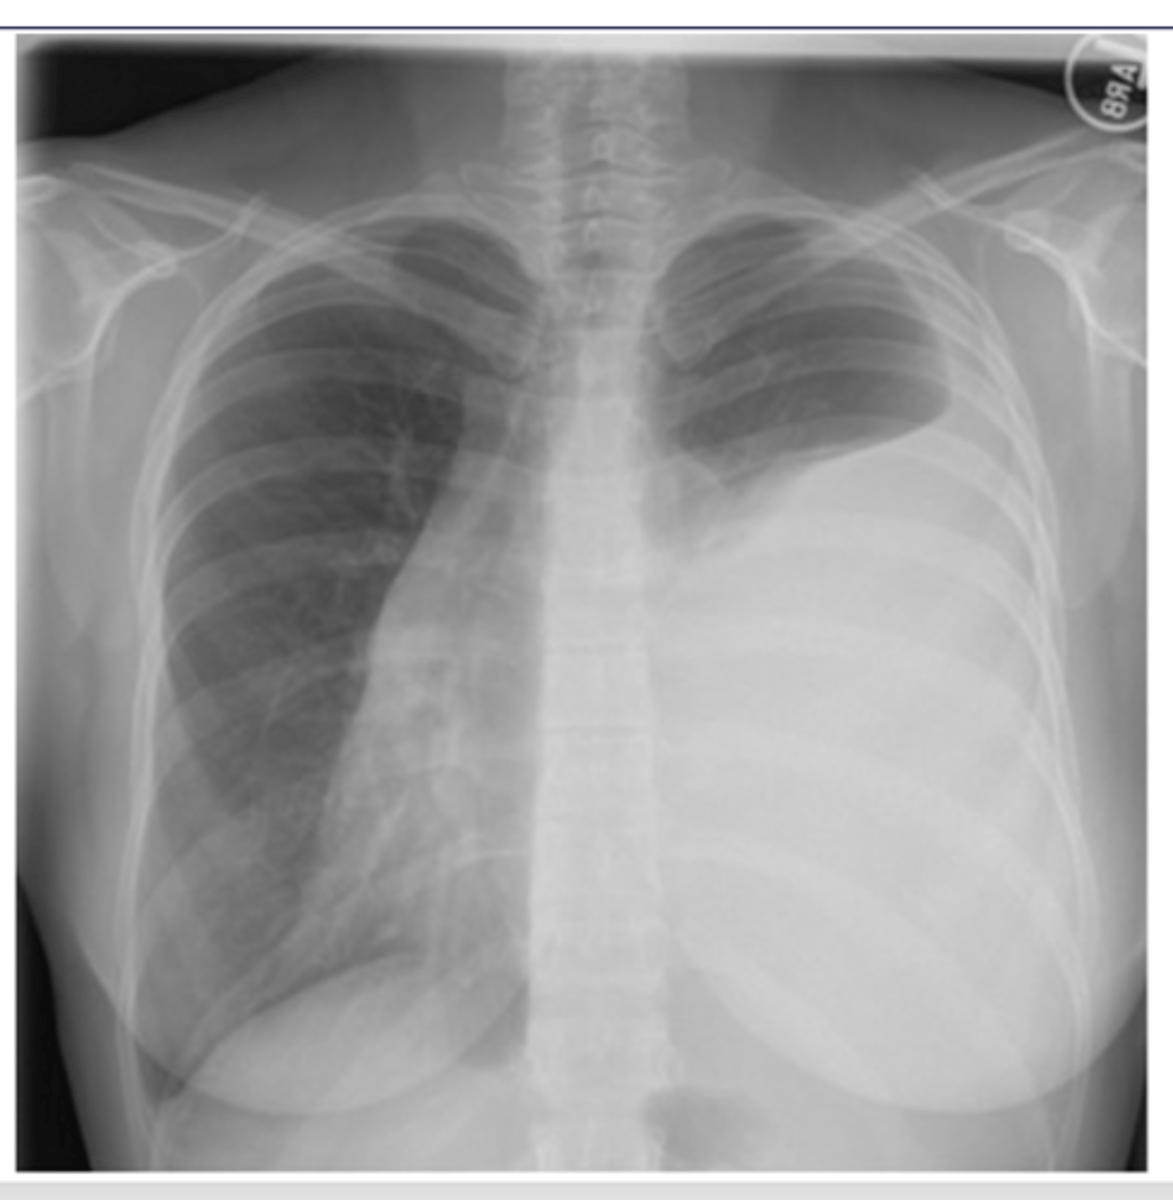

Pleural effusion

-fluid build up is pushing the mediastinum laterally which causes the t spine to be more visible

-can use lateral decubitus position to confirm presence of effusion/fluid